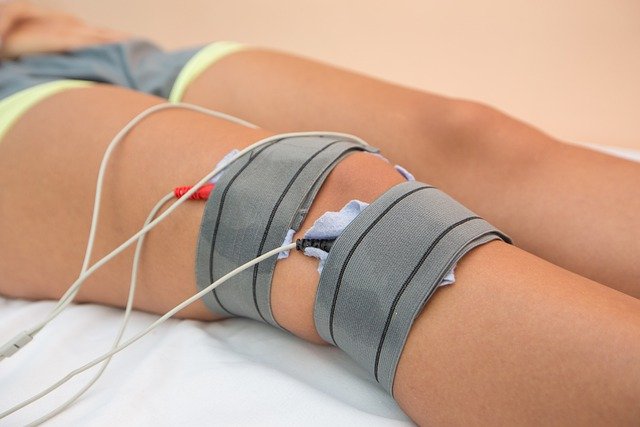

무릎관절염이 의심되면 병원에 내원하셔서 연골 주사나 처방을 받아 약을 드시면 좋습니다.